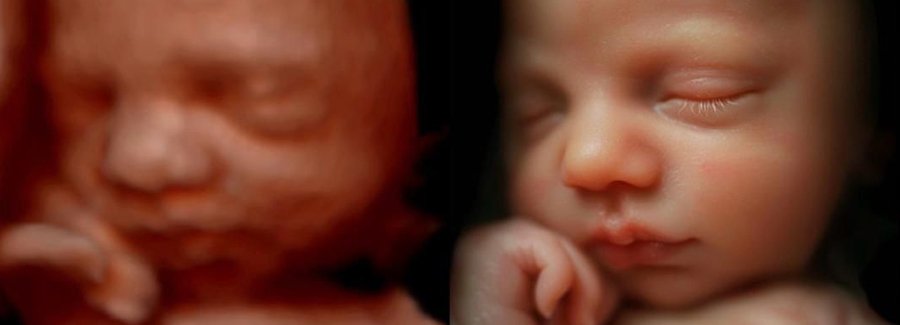

The best time to see your baby’s face in 5D/HD is between weeks 25 and 30 of your pregnancy.

Often referred to as 5D, HD or FRV (fetal realistic view), 5D/HD is the newest development in pregnancy imaging. It captures and combines high definition volume data to create automated images with amazing color and clarity so you can see your baby as though you were looking from inside the womb.